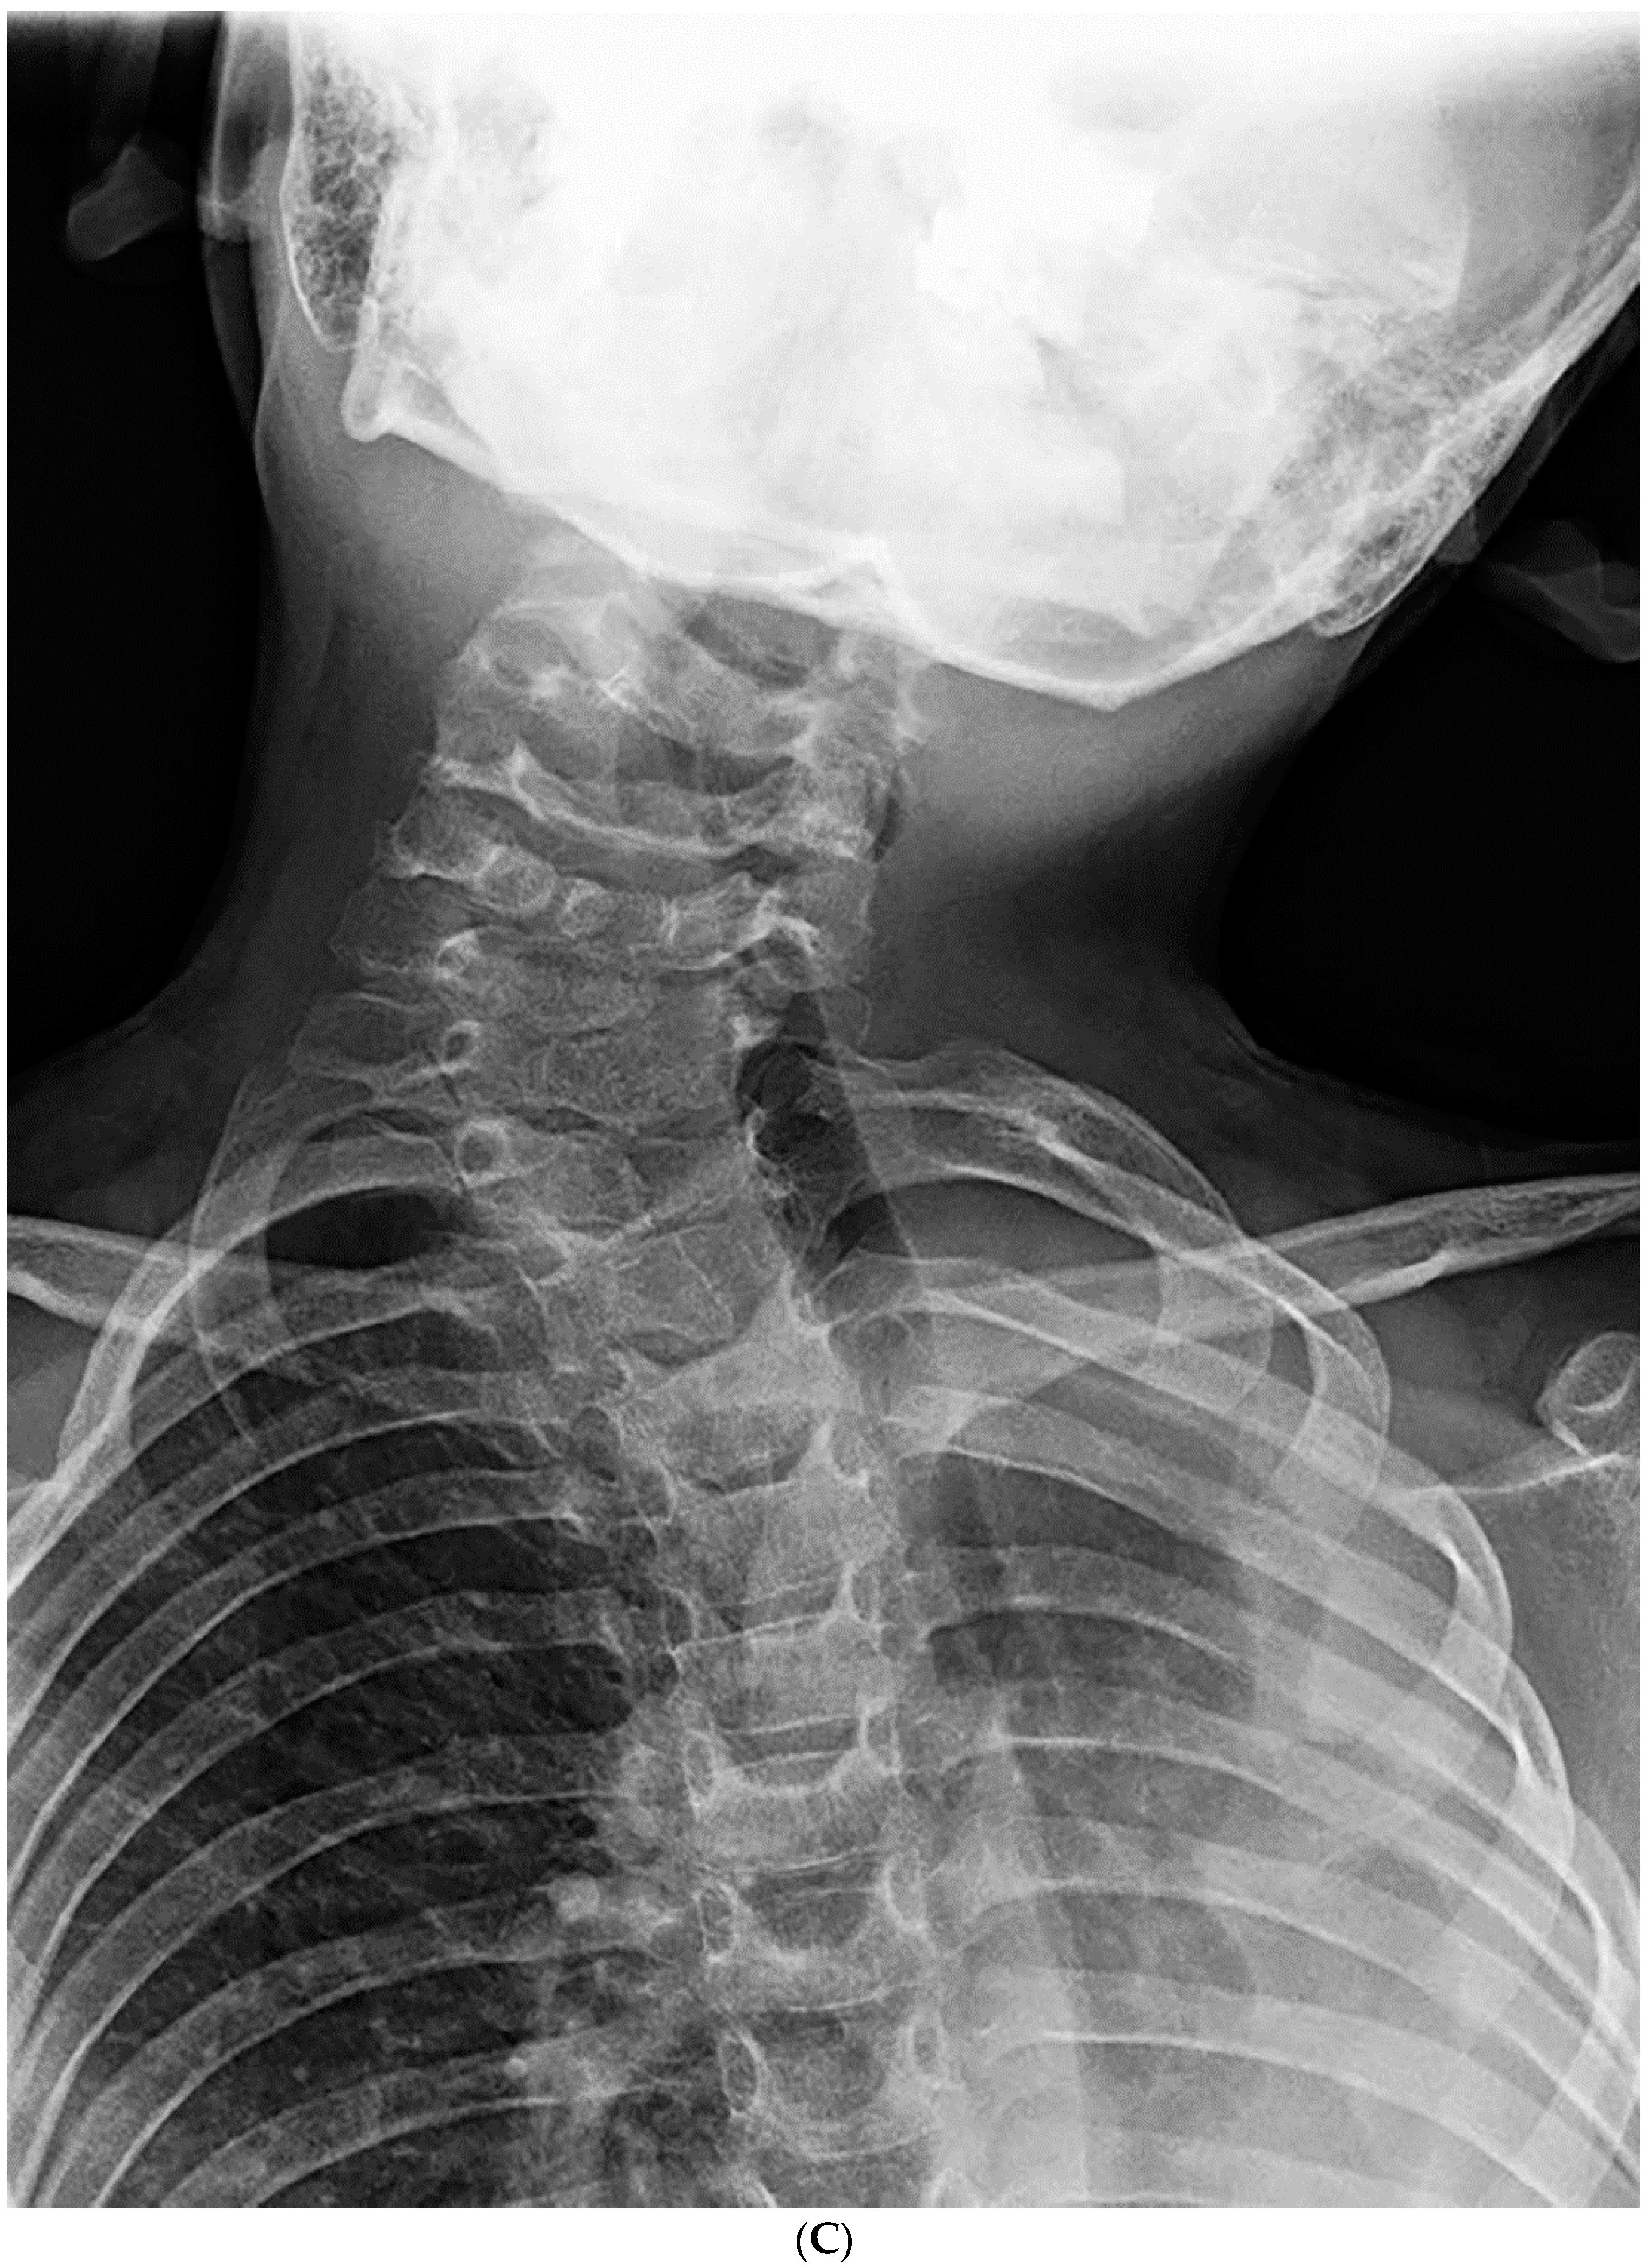

Risk Factors for Progression of Cervical Congenital Scoliosis and Associated Compensatory Curve Behavior

3. Results